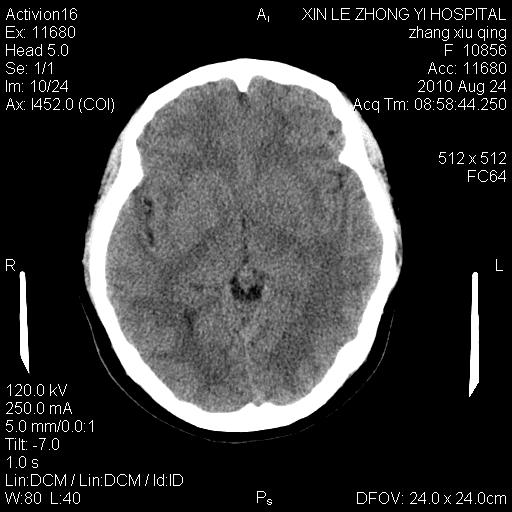

标题: CT28569:看看鞍上池正常吗 [打印本页]

标题: CT28569:看看鞍上池正常吗

女 24 偶有头晕

怎么这么多伪影?我感觉没什么特别异常哦,是不是伪影所至呀

病史?感觉有水肿,炎症或转移

伪影多,建议行mri!

未见明显异常,必要时可作mri

没什么!只是扫描层面与听眦线不平行

伪影干扰下,所见无水肿、无占位,建议定期复查。